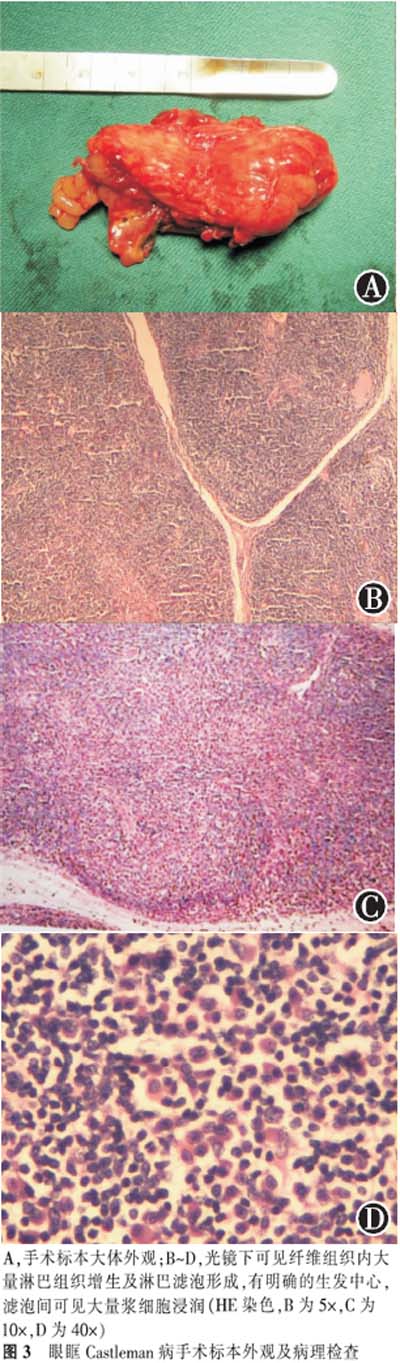

患者,男,77岁,农民,因右眼下睑肿物3年,明显增大3个月而入院。患者于3年前无意中发现右眼下睑肿物,大小1.5 cm×2.0 cm,质软,无红肿、疼痛,不伴有复视、流泪、视力下降等眼部不适,曾就诊于当地县医院,诊断不详,给予激素等药物治疗后肿物变小。1年前发现肿块又稍增大,近3个月明显增大,同时伴眼部红肿、流泪等症状,遂转诊至我院。既往史:高血压病史10余年,糖尿病史1年,1年前患脑血栓。眼部检查:右眼视力 0.3,左眼视力0.5,右眼球稍突出,内转、上转稍受限,右眼下睑可见4.5 cm×3.5 cm类圆形肿物,边界尚清,质软,不活动,结膜充血,角膜清亮,前房深度正常,瞳孔正常大小,对光反应存在,晶状体稍混浊。眼底检查示:视乳头边界清,色可,视网膜血管走形正常,无出血和渗出,黄斑中心反光可见。左眼底未见明显异常。眼位检查:右眼外斜15°。双眼眼压17.30 mmHg。眼球突出度:右眼18 mm,左眼16 mm,眶距112 mm。辅助检查:眼眶CT扫描示右眼眶球后内直肌与视神经间局限性软组织肿块,向前下延至下眼眶并累及眼睑,下直肌被推向外侧,视神经无增粗,眼球稍突出(见图1)。胸腹部CT扫描未见明显异常。眼眶MRI显示右眼眶内眼球后下方可见一等T1等T2信号影,其内信号不均匀,压脂序列呈高信号,病变向眶外突出,与筛窦和视神经分界不清,内、下直肌显示不清,眼环完整,眼球向上、前、外移位,视神经无增粗;增强扫描肿物明显强化(见图2)。